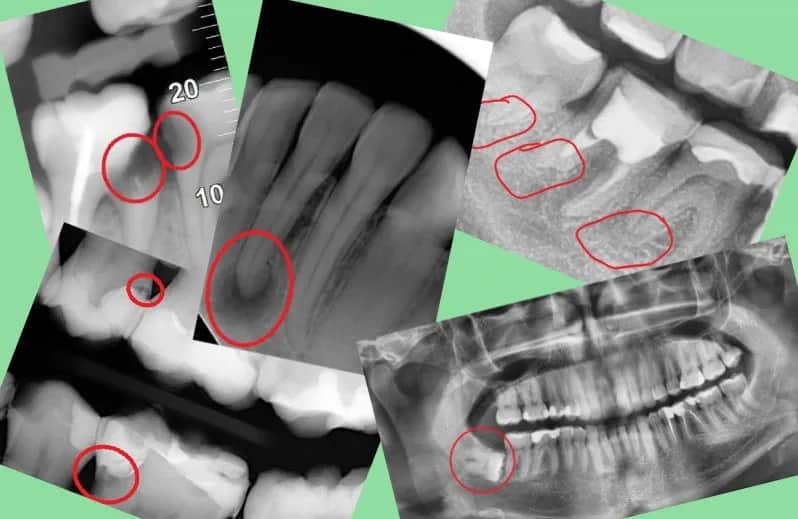

Poznaj najważniejsze skutki uboczne leczenia kanałowego zęba, takie jak ból, obrzęk i powikłania. Dowiedz się, jak zapewnić skuteczną regenerację zęba po leczeniu.